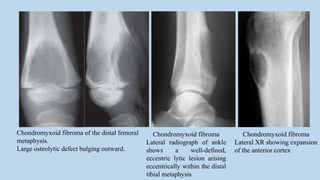

Chondromyxoid fibroma of the distal femoral

metaphysis.

Large osteolytic defect bulging outward.

Chondromyxoid fibroma

Lateral radiograph of ankle

shows a well-defined,

eccentric lytic lesion arising

eccentrically within the distal

tibial metaphysis

Lateral XR showing expansion

of the anterior cortex